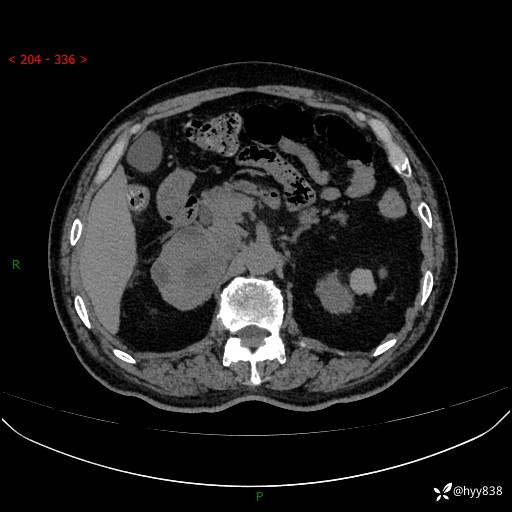

【患者信息】:76岁/男

【主诉】:检查发现右侧肾上腺占位6天

【现病史及既往史】:患者6天前体检发现右侧肾上腺占位,无腰痛,无放射痛,无尿频、尿急、尿痛及肉眼血尿,无畏寒、发热,无恶心、呕吐,今为求进一步治疗,遂来我院就诊,门诊拟“右侧肾上腺占位”收住入院。 起病以来,患者精神、饮食、睡眠可,大小便如常,体力体重无明显变化。

【检查】:肾上腺CT平扫+增强